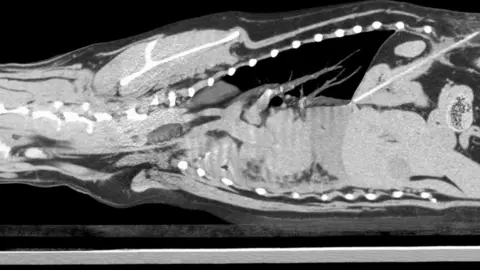

Dick White ReferralsA dog was left fighting for its life after swallowing a wooden kebab stick.

Vets carried out two scans before finding the cause of Sweep's distress - the wooden stick which, still whole, had gone through his stomach.

Dick White ReferralsImmediate surgery was needed as the kebab stick was deemed "life-threatening" to the dog.